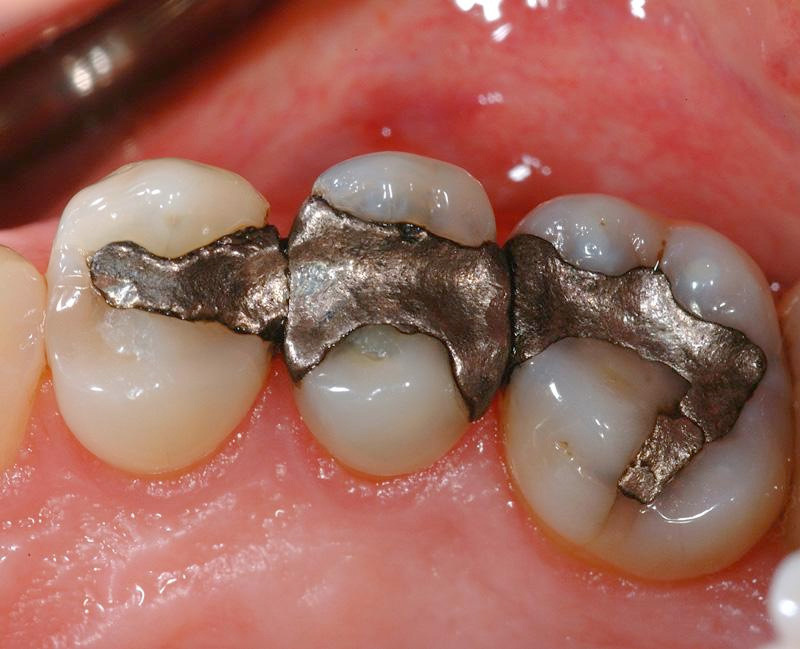

Three amalgam fillings.As you see in the image above, dental amalgam fillings are dark grey in color, and we have just seen that they are 50% mercury. So, they don't look like a natural tooth, and they have potential problems with toxicity. Why would any dentist want to use this material to fill tooth cavities?

In the top left hand corner of the next image, you will see a broken cusp next to a big amalgam filling. There is no decay. The expansion of the amalgam is responsible.